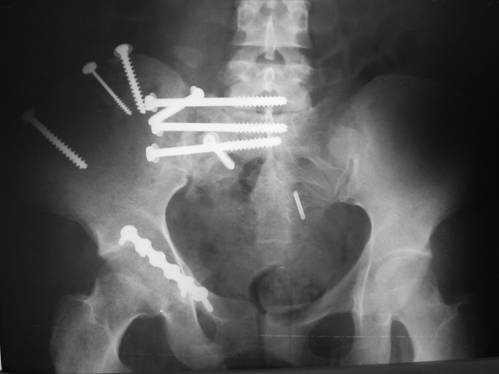

Дорогой Андрей. Мы имеем дело с комбинированной (ротационно и

вертикально) нестабильностью таза со смещением правого гнемипелвиса. При

таких переломах, фиксация только переднего полукольца вне зависимости от

метода фиксации, как уже было сказано Djoldas Kuldjanov, M.D., не может

создать адекватной фиксации. И перелом пластины был вполне ожидаемым

после активизации пациента. Смещение сохраняется, и по-видимому не 2

см., а все 4, если не более. Разница всего (+2 см) по конечностям как вы

указываете, скорее скомпенсировано позвоночником и протезом.

Пациентка С.26 лет. Травма за 6 месяцев до поступления

Укорочение правой нижней конечности до 10см

23.09.2003. Одновременный остеосинтез переднего и заднего тазовых полуколец

Результат через 10 дней  и  8месяцев после операции